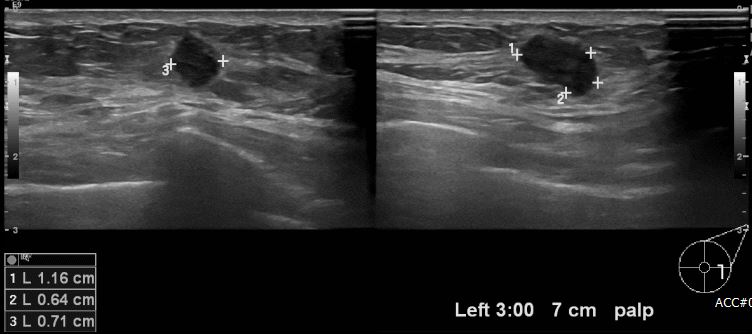

건강검진상 이상소견으로 내원하신  60대 여성분으로  좌측유방 3시 방향에서 7cm 떨어진 거리의 만져지는 멍울 조직검사 시행하여 좌측 침윤성 유관암 진단되었습니다.